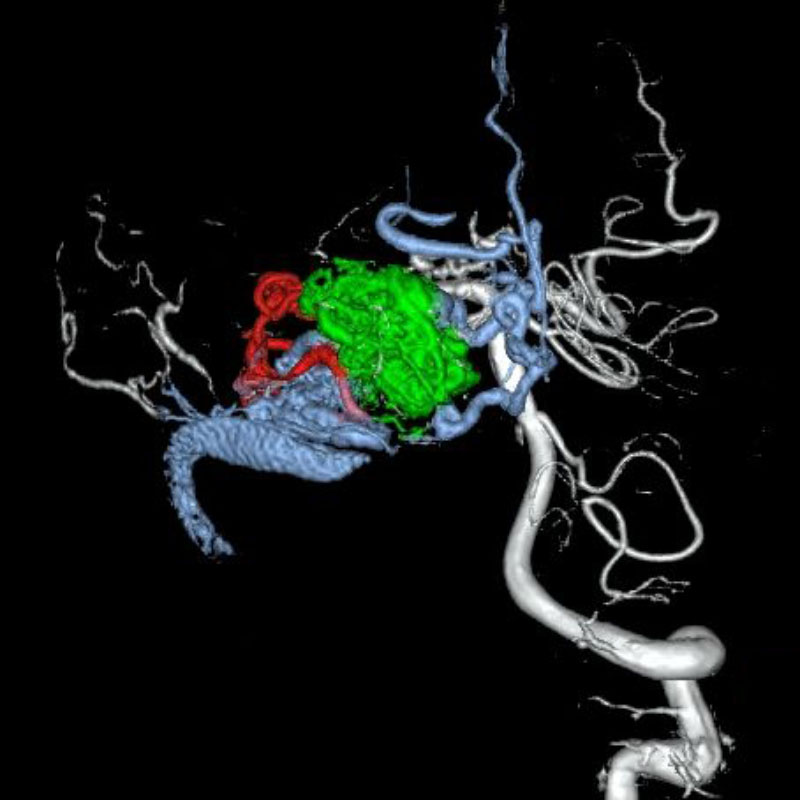

脳動静脈奇形

血管塞栓術

松田/濵田/元永